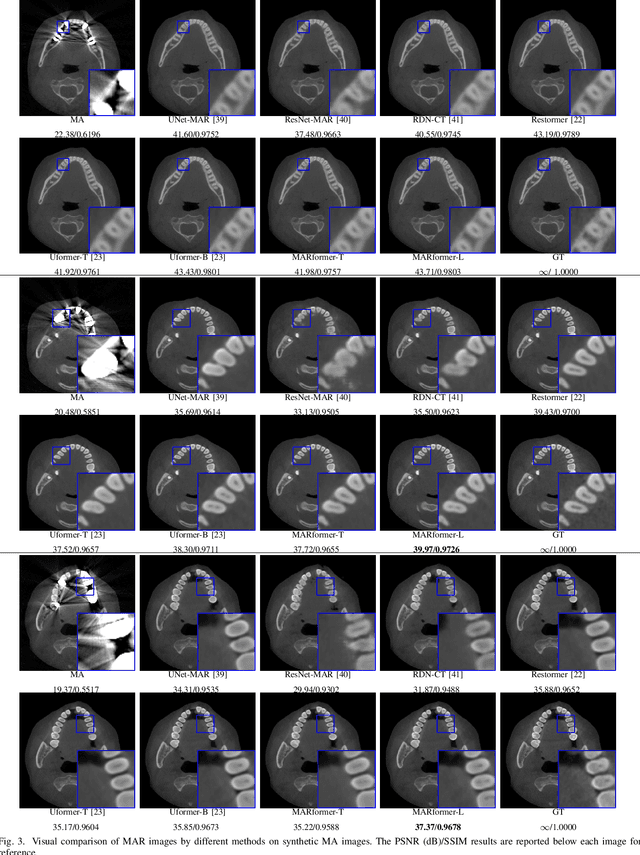

Abstract:Cone Beam Computed Tomography (CBCT) plays a key role in dental diagnosis and surgery. However, the metal teeth implants could bring annoying metal artifacts during the CBCT imaging process, interfering diagnosis and downstream processing such as tooth segmentation. In this paper, we develop an efficient Transformer to perform metal artifacts reduction (MAR) from dental CBCT images. The proposed MAR Transformer (MARformer) reduces computation complexity in the multihead self-attention by a new Dimension-Reduced Self-Attention (DRSA) module, based on that the CBCT images have globally similar structure. A Patch-wise Perceptive Feed Forward Network (P2FFN) is also proposed to perceive local image information for fine-grained restoration. Experimental results on CBCT images with synthetic and real-world metal artifacts show that our MARformer is efficient and outperforms previous MAR methods and two restoration Transformers.